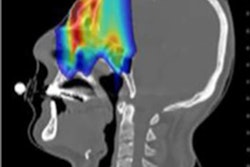

Simulated proton-CT, helium-CT, and carbon-CT images. Image courtesy of Sebastian Meyer.Meyer presented results from FLUKA Monte Carlo simulations comparing proton, helium-ion, and carbon-ion CT for proton therapy planning. He described the simulation of ion-CT images at 2 mGy physical dose using an ideal single-particle tracking detector for two head-and-neck cases treated with scanned proton pencil beams.

The reconstructed proton-CT, helium-CT, and carbon-CT images were similar in appearance although helium-CT and carbon-CT were slightly noisier, and all displayed comparable dose calculation performance.